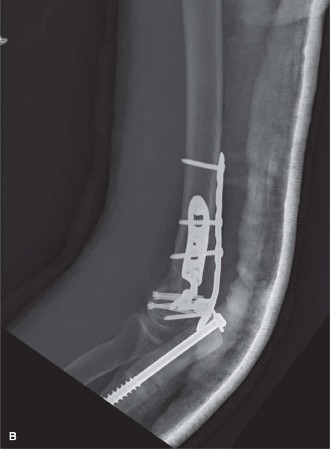

The surgeon elects to use an olecranon osteotomy and performs ORIF using orthogonal plating in combination with several headless compression screws to address the capitellum fracture. The post-op radiographs are shown in Figure 6–12A and B.

Figure 6–12 A–B

The correct answer is (D). It is extremely common to lose some elbow range of motion after elbow fractures, particularly with distal humerus fractures. This loss of motion may be due to a number of variables including articular incongruity, capsular contractures, loose bodies, heterotopic ossification, and/or prominent hardware. The average flexion contracture following ORIF of distal humerus fractures is 20 to 25 degrees, and an expected total arc of motion is 100 to 110 degrees. Symptomatic hardware is common as well, especially with an olecranon fracture or osteotomy. In this case, however, the olecranon osteotomy was fixed with a cancellous screw and washer which requires hardware removal less frequently than other fixation methods such as tension band wiring, where wire back-out is a frequent issue. Another complication, specifically associated with an olecranon osteotomy, is nonunion of the osteotomy site.